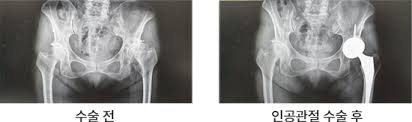

고관절 수술(고관절 전치환술, 인공관절 치환술 등)은 말기 관절염, 골절, 골수 괴사 등 다양한 원인으로 시행됩니다. 수술 후 회복 기간은 수술 방식, 환자 상태, 재활 병행 여부에 따라 다르지만, 일반적으로 3개월~1년 정도 소요됩니다. 본 포스트에서는 수술 종류, 회복 단계, 재활 프로그램, 주의사항, 일상 복귀 팁을 2,500자 이상으로 상세하게 안내합니다.

- 고관절 전치환술(Total Hip Arthroplasty, THA): 골관절염이나 류마티스 관절염, 골절 등에 널리 사용되는 방식으로, 관절 전체를 인공 관절로 교체합니다.

- 정기 검진: 엑스레이 또는 CT로 인공관절의 상태 확인